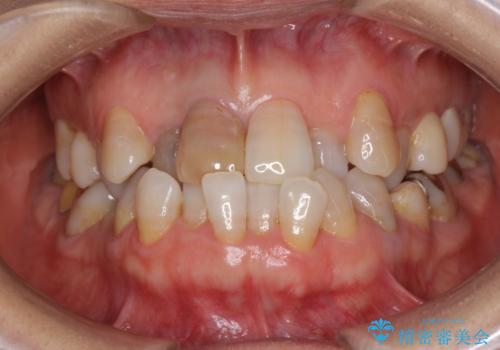

変色した前歯のオールセラミック治療

- 前歯の変色が気になるとのことで来院された患者様です。

歯並びに問題があるため、矯正治療の提案をしましたが、変色の改善のみ(オールセラミッククラウンによる審美補綴治療のみ)とすることにしました。

矯正治療を行う必要性は理解いただきましたが、「今さら歯並びを整えても・・・」という思いが強かったようで、何度もカウンセリングを行った結果、審美補綴治療のみとなりました。

お粗末な根管治療、根管充填がされていたため、補綴治療を行うにあたり根管治療を行いました。